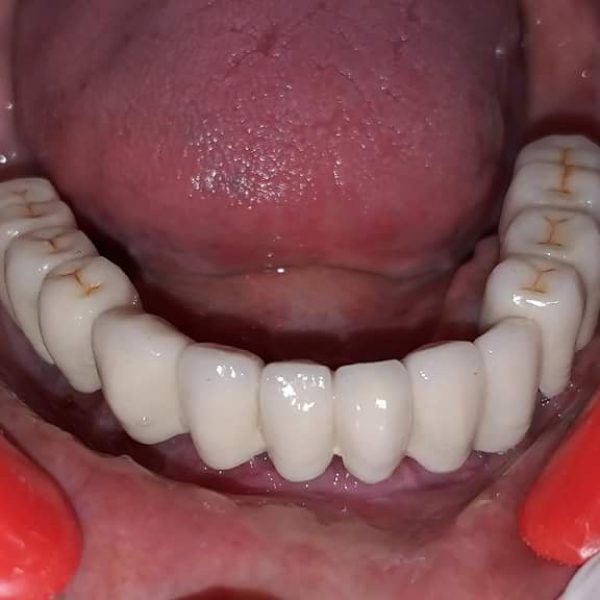

Full Mouth Rehabilitation

Full mouth rehabilitation involves comprehensive procedures tailored to individual needs, addressing issues such as missing teeth, bite problems, damaged teeth, and overall oral health concerns to achieve a harmonious and functional smile. Experience top-tier full mouth rehabilitation at Sanjivani Dental Hospital in India.